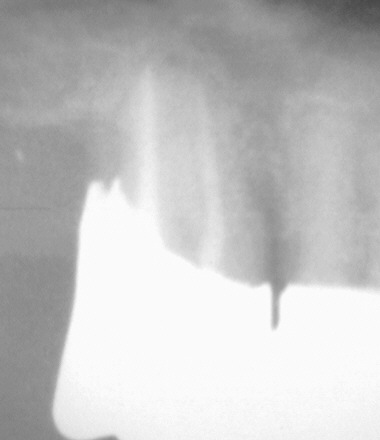

Das gilt sowohl für Erstversorgungen als natürlich auch für Revisionen alter, insuffizienter Wurzelfüllungen wie in diesem Beispiel.

Galerie: